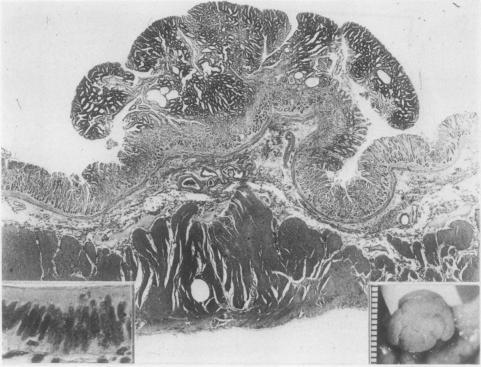

A total of 611 gastric polyps from 275 cases were studied and were classified into four subtypes. Type I was the most common type and types II, III, and IV were less common. Type I and II, considered to be non-neoplastic polyps because of the absence of dysplasia, showed an extremely low malignant potential. Type III showed a two layer structure, the upper layer of which was composed of dysplastic epithelia. This type showed a low malignant potential despite the dysplasia. The type IV polyp showed macroscopical and histological findings similar to those of colonic adenoma. This type was considered to be truly neoplastic and to be the most important of the four subtypes because of its high malignant potential. Type III and IV should be clearly separated and treated differently.

对来自275例患者的611个胃息肉进行了研究,并将其分为四种亚型。I型是最常见的类型,II型、III型和IV型较不常见。I型和II型由于没有发育异常被认为是非肿瘤性息肉,其恶性潜能极低。III型呈现两层结构,其上层由发育异常的上皮组成。尽管存在发育异常,但该型恶性潜能较低。IV型息肉在大体和组织学表现上与结肠腺瘤相似。该型被认为是真正的肿瘤性息肉,由于其高恶性潜能,是四种亚型中最重要的。III型和IV型应明确区分并进行不同的治疗。